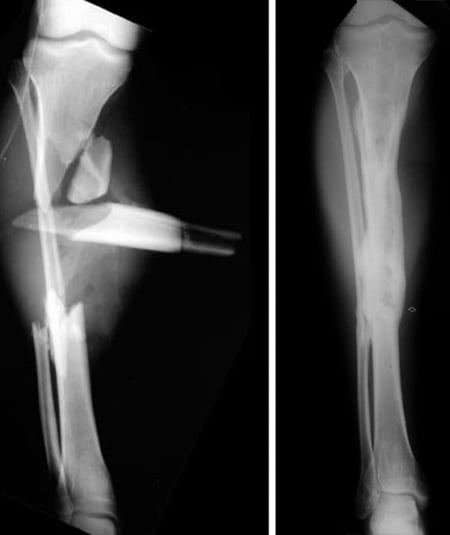

Anteroposterior (front to back) and lateral (side view) X-rays of the realigned femur and tibia one year after surgery.